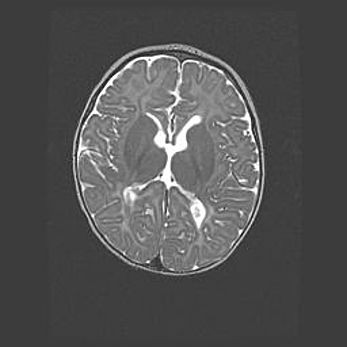

Лейкомаляция с кистозно-глиозной дегенерацией головного мозга.

Возраст: 2 месяца 25 дней

Вес: 6400 г

Окружность головы: 40 см

Срок гестации: 41 неделя

Лейкомаляцию относят к ишемически-гипоксическим повреждениям головного мозга, диагностируемым у новорожденных. При лейкомаляции в головном мозге обнаруживают очаги некроза, возникшие после тяжелой гипоксии и нарушения кровотока. В процессе морфогенеза очаги проходят три стадии: 1) развития некроза, 2) резорбции и 3) формирования глиозного рубца или кисты. Перивентрикулярная лейкомаляция (ПЛ) встречается примерно в 12% случаев среди новорожденных, обычно – у недоношенных детей, причем, частота ее зависит от массы, с которой младенец появился на свет. Наибольшее число малышей страдает лейкомаляцией, если масса при рождении 1500-2500 г.